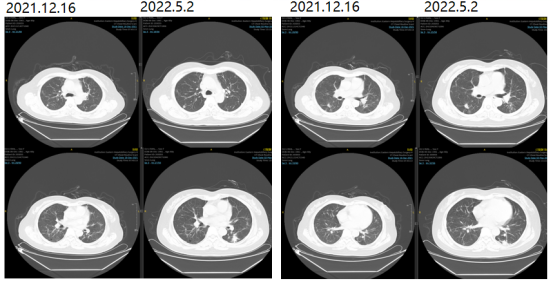

2021-09-04、2021-10-12、2021-11-3、2021-12-15再次原方案化疗4疗程。

2021-12-16评估疗效PR。

2022-05-02复查胸部CT提示两肺多发转移瘤,较前进展。PFS2:11月。

图3影像学复查结果

2022.5.2影像学复查结果